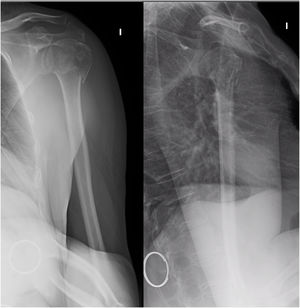

Material y métodoSe trata de un estudio prospectivo, observacional, de una serie de casos consecutivos: pacientes que acudieron al Servicio de Urgencias de nuestro hospital y que fueron diagnosticados de fractura del extremo proximal del húmero entre el 1 de marzo y el 30 de junio de 2017. Los criterios de inclusión en el estudio fueron: pacientes mayores de 18 años, de la población de referencia de nuestra área sanitaria, que presentasen una fractura del extremo proximal del húmero y que aceptasen voluntariamente participar en el estudio y realizar un estudio neurofisiológico (una EMG y un electroneurograma) como prueba diagnóstica añadida al tratamiento convencional de la fractura, es decir, el tratamiento conservador o quirúrgico. La decisión de tratamiento (conservador o quirúrgico) en los pacientes incluidos en el estudio no cambió por el hecho de entrar en el estudio; recibieron el tratamiento habitual que realizamos durante la asistencia clínica. El estudio neurofisiológico se programó a los 20 días de la fractura aproximadamente, pues se considera que es el momento óptimo para encontrar -de manera precoz- una lesión de este nervio con esta prueba. Esto se hizo así en los casos que recibieron tratamiento conservador con inmovilización con cabestrillo. El estudio neurofisiológico que se realizó fue tanto una EMG como un electroneurograma. Se hizo comparación con el brazo contralateral como control. Además, en los casos en los que se apreció lesión del nervio axilar, se repitió la EMG y el electroneurograma al mes, como control. La neurofisióloga que participó en el estudio es una profesional con amplia experiencia. Los criterios de exclusión fueron: enfermedades que pueden afectar el registro EMG de base (diabetes mellitus [DM], polineuropatía, miopatía, enfermedad de la motoneurona, hipotiroidismo o hipertiroidismo), tratamientos anticoagulantes como el acenocumarol o la warfarina, o demencia avanzada y otras enfermedades que puedan dificultar la colaboración del paciente durante el estudio neurofisiológico. Tampoco se incluyeron pacientes que presentasen fracturas patológicas ni aquellos que fueron atendidos en Urgencias de nuestro Hospital, pero tuvieron el seguimiento en otro centro. Por último, no se incluyó ningún paciente que hubiese sido operado previamente de ese hombro (fig. 1).

Se realizó una revisión de las radiografías simples de cada paciente. En los casos en los que se optó por un manejo quirúrgico o aquellos en los que la radiografía simple planteaba dudas sobre la indicación terapéutica sí que se realizó una tomografía axial computarizada (TAC) para completar el estudio.

En la valoración inicial, las fracturas se clasificaron según la clasificación de la AO (Arbeitsgemeinshaft für Osteosynsthesefragen, Asociación de Grupo de Trabajo para el Estudio de la Fijación Interna de las Fracturas) en tipo AO11A, unifocal extraarticular; AO11B, bifocal extraarticular y AO11C, articular (fig. 2), y se subclasificaron según los grupos de esta clasificación (tabla 1).